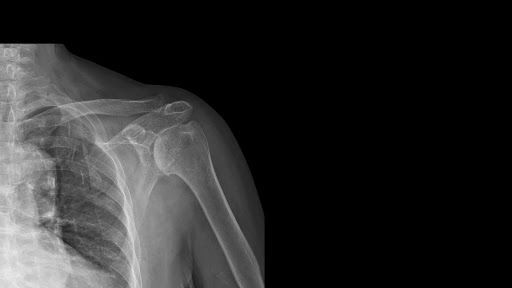

Como é feito o diagnóstico

A investigação da dor no ombro à noite começa com uma avaliação clínica.

O médico analisa a localização da dor, os movimentos que pioram o sintoma e a presença de limitação funcional. A partir dessa análise, decide quais exames são necessários.

Os principais exames incluem:

Ultrassom, que permite avaliar os tendões em movimento

Ressonância magnética, indicada para identificar lesões estruturais

Radiografia, útil para observar alterações ósseas e calcificações

A escolha depende da suspeita clínica e da evolução dos sintomas.